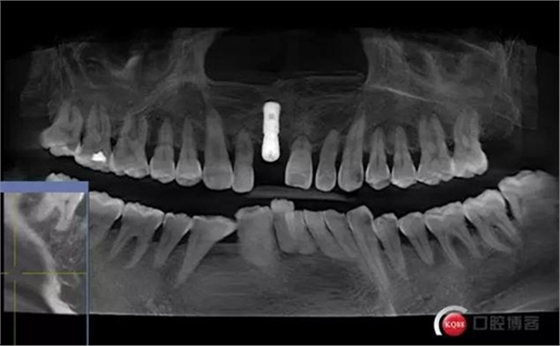

術后CBCT